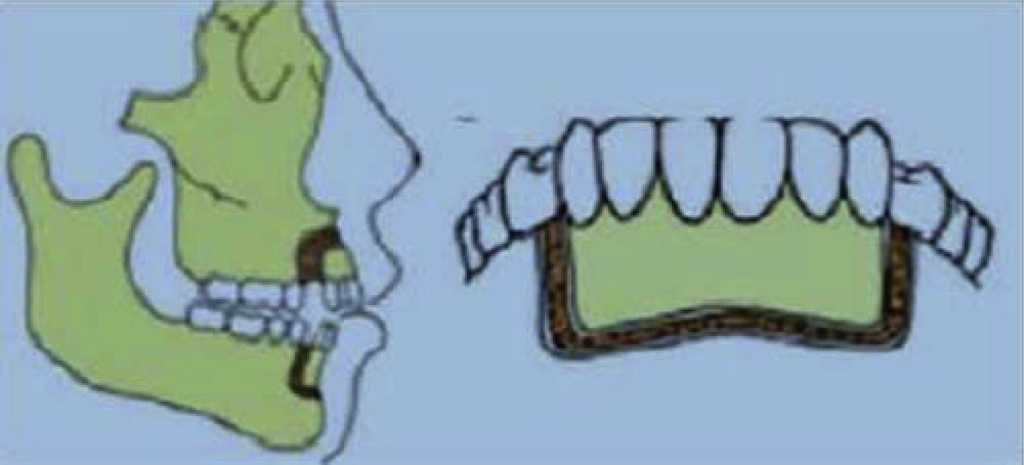

Fast orthodontics (Chung 1975 and 1978)

A new technique called Fast Orthodontics was proposed by Chung between 1975 and 1978. This technique combined cuts with orthopedic forces exerted with intra-osseous anchoring devices which normally were mini-plates or implants. The surgical cut had a «C» shape and biologically attempted to generate compression-osteogenesis in the osteotomized segment (Figures 3 and 4).4 Correction of anterior protrusion with or without open bite was among suggested indications.6

Disadvantages of this technique were its invasive nature,4 and the fact that osteotomies were performed at different surgical times with lapses of 2 to 3 weeks separating them.6

Limitations for this technique were the sort of removable devices used at the time which were insufficient to provide required forces after were insufficient to provide required forces after corticotomies procedures; said forces were the key factor to achieve treatment success.5